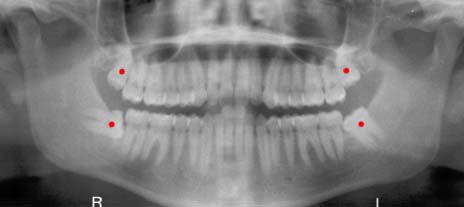

Agzimdan kopuklu kanlar puskurte puskurte bir muddet kahkaha attiktan sonra sol alt 20 lik yas disimin ciktigi, cikarken de kesesini patlattigi ve kanama yaptigi gibi dissel bilgileri ogrendim

“Cekmeye gerek yok cok saglikli cikmis kalsin ama dis etleriniz cok cep yapmis” dedi

Damagimda dis var dedim. Gordum dedi. Gormemesine imkan yoktu ki. Cunku damagimdaki dis neredeyse burnum ile ani buyuklukte.

Ben sanarsinki 5 sene discilik okumusum…”tabi onu bi cene cerrahinin cikartmasi lazim gomuk falan koku on dise kaynamis” dedim.

“Yoo gomuk falan degil tamami cikmis normal dis gibi cekicem cok kolay is” dedi

Bunca sene o disin oradan cekilmesi icin alt cenemin tamamen sokulup cok buyuk bir ameliyata ve vinc yardimina ihtiyac duyulacagini dusunen ben pekte inanmamis tavirlarla saga sola baktim. Pedro ole demiyo amaaaaaaa